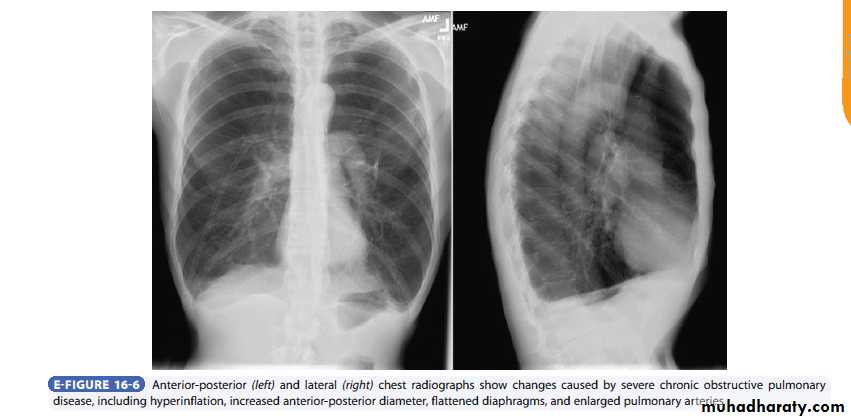

Radiology

Chest x-rayHyperlucency

Vascular attenuationHyperinflation (emphysema).

High-resolution CT is the most sensitive and specific technique for detection of pulmonary emphysema and grading of its severity.

It is not recommended for routine clinical assessment of COPD, it may be used to evaluate the feasibility of lung volume reduction surgery.